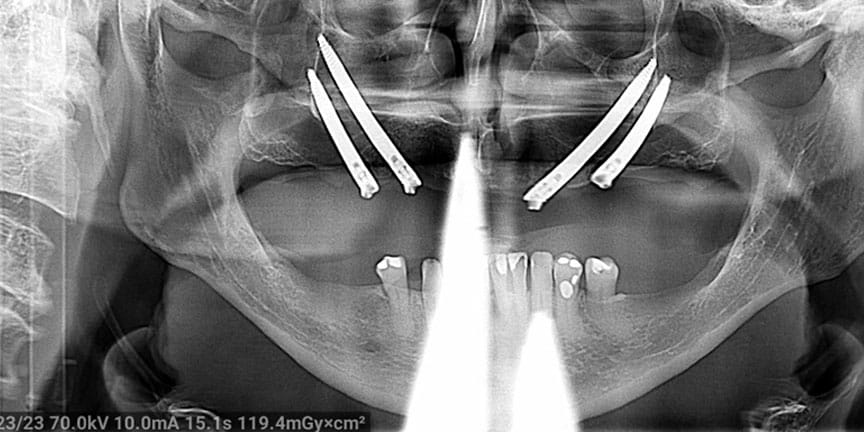

Difficult Cases

We treat patients when other providers cannot manage.

Severe Bone Loss